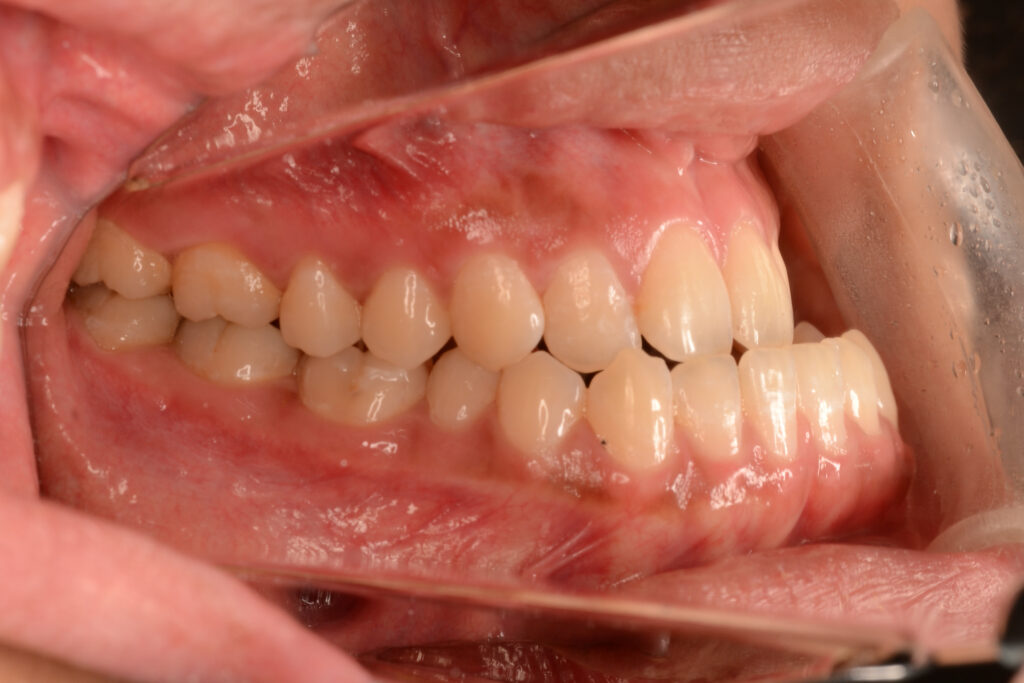

受け口を矯正治療だけで治せるケースは、受け口になっている要因が叢生(でこぼこ)であったり、受け口の程度が軽度で横顔を気にしていない場合、骨格的な要素がない場合です。

ご自身で顎を後ろに引いて噛んでみたときに、上顎と下顎の前歯が頭で噛める場合は、骨格的要素は軽度と言えるかもしれません(あくまで参考ではありますが…)。

上記の場合であれば、矯正治療単独で受け口の改善は可能ですが、小臼歯抜歯が必要であったり、歯科矯正用アンカースクリューの併用が必要であったりします。

当院で受け口を矯正治療単独で治した事例 ←リンク